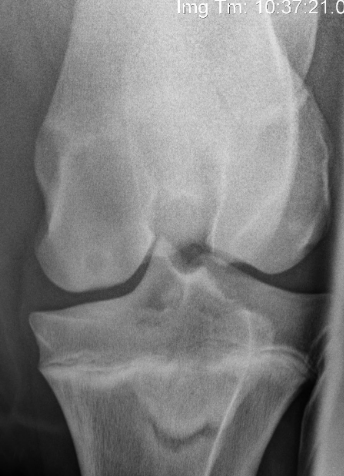

32

which is normal and which is abormal. what do you see here?

the one on the left is normal with a nice fat pad in the joint which appears more radiolucent than soft tissue orfluid. in the one on the right, there is joint effusion as seen by the increase in opacity where the fat pad should normally be, and the fat pad is displaced cranially.

33

it can be difficult to identify cruciate ligament injuy sometimes. What is sometimes the only radiographic finding?

joint fluid/effusion

34

other than joint effusion, what are some other radiographic signs of cruciate lig injury?

osteophyte formation and cranial displacement of the tibia